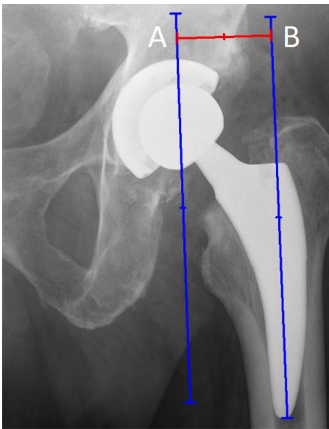

在前后位X线片上,下肢长度差异表示为穿过双侧泪滴点下缘的直线到相应小转子尖 (tip of the lesser trochanter) 的垂直距离之差。

下肢长度差异测量。A 和 A' 位于小转子尖水平。 B 和 B' 位于泪滴点下缘水平。 AB 和 A'B' 线是穿过泪滴点下缘的直线到相应小转子尖的距离。 AB 与 A'B' 长度之差即为下肢长度差异。